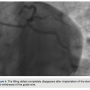

defect in the LMCA and proximal CX artery was encountered that was refractory to nitroglycerin and resembled coronary dissection, due to LMCA trauma from the EBU catheter (Figure 2). The patient had no clinical symptoms or EKG changes. A “pleating artifact” in the LMCA and Cx artery, induced by the stiff structure of the extra support guidewire, was felt to be likely due to the acute angle of the origin of CX artery from the LMCA. The guide wire was partially withdrawn and the filling defect decreased (Figure 3). A stent was appropriately placed into the in-stent restenosis without any complication. The filling defect completely disappeared after complete withdrawal of the guide wire (Figure 4).

“Pleating artifact” is a benign pathology rarely seen during coronary interventions. It can occur

when a curved artery is straightened by a stiff guide wire. Several features of this benign pathology discriminate it from real pathology. It may occur in the irrelevant segment of the vessel, is refractory to nitroglycerin, and resolves when the guide wire is partially or completely withdrawn. It should be distinguished from coronary spasm, dissection, or true stenosis in order to avoid unnecessary stenting or surgery.